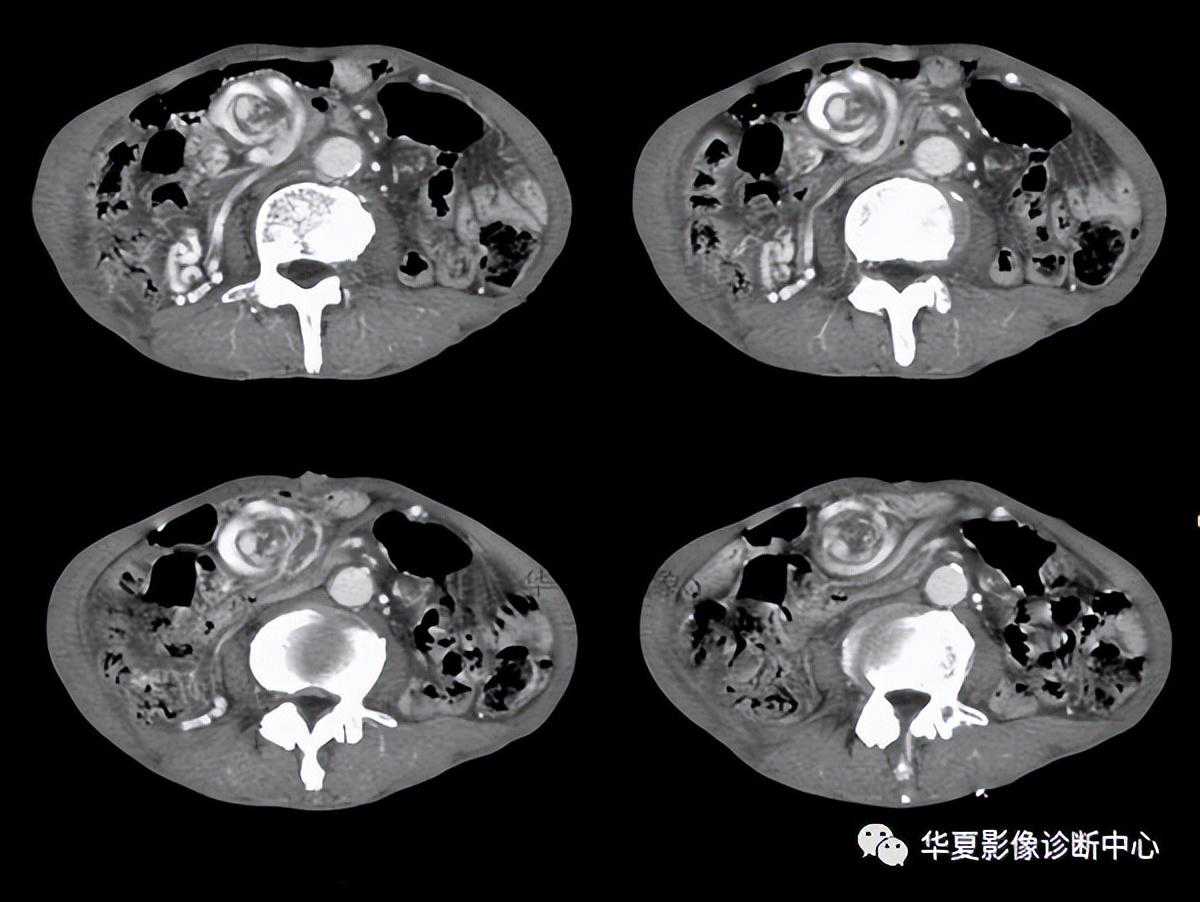

031:箭头征

阑尾炎CT的直接征象是阑尾形态的异常,表现为阑尾外径增粗和阑尾壁的增厚。正常阑尾的直径一般3~5mm,有些报道在阑尾腔内无对比剂的情况下,正常阑尾外径可达11mm。急性阑尾炎患者的阑尾平均直径达11mm。不能单凭阑尾增粗(>6mm)或阑尾壁增厚(>3mm)来诊断阑尾炎,必须结合其他征象综合考虑。

“箭头”征阑尾炎的一个比较典型的CT表现,是造影剂汇集在盲肠尖端(阑尾起始部)形成的箭头样、鸟嘴样改变,是阑尾炎症蔓延到盲肠尖肠壁的结果。如果在盲肠的尖端汇集的不是高密度的造影剂而是气体,那么显示的就是空箭头征。如果造影剂汇集于结肠憩室的口部,也会显示这样的征象。箭头征也见于急性阑尾炎的CT增强扫描中,急性阑尾炎患者的阑尾血流比率比正常肠道高,增强扫描时可见其强化。部分患者由于炎症时肠壁血管内血栓形成,使局部血流受阻,阑尾血流比率可等于或低于正常肠道,甚至无血流灌注,CT上阑尾表现为等密度,低强化或无强化;另外阑尾炎时,其邻近肠管可继发炎症,局部血流增加,有时CT上可见局部盲肠壁增粗,强化时增强,似箭头一样指向病变阑尾。“箭头”征是造影剂汇集在盲肠尖端(阑尾起始部)形成的箭头样、鸟嘴样改变,是阑尾炎症蔓延到盲肠肠壁的结果。见到此征象,有文献报道,阑尾炎的特异度几达100%。有些患者由于炎症较轻,肠道血流可无明显改变;也有些病例,可能是肠壁部分血流受阻,与炎症引起的血管扩张相抵消。因而其血运明显受阻,局部造影剂减少所致。

阑尾粪石可能增强阑尾穿孔的机会,当发现阑尾钙化或阑尾粪石,同时合并阑尾周围炎时,是诊断阑尾炎的可靠征象。阑尾粪石也可出现在阑尾穿孔形成的脓肿或蜂窝织炎内。阑尾周围炎表现为阑尾周围脂肪组织中条索状、斑片状密度增高影(称脂肪条带征)、结肠后筋膜增厚、阑尾周围液体渗出,局部形成脓肿。阑尾周围炎只是阑尾炎的一种主要间接征象,不能单凭此诊断阑尾炎。阑尾周围炎性反应或右下腹脓肿提示阑尾炎,但Crohn病、盲肠炎、憩室炎、肿瘤穿孔和盆腔炎等亦可有相似的表现,应与之鉴别。通过对阑尾强化程度和阑尾周围炎症改变对急性阑尾炎的严重程度作出初步评估,指导临床治疗。正确选择治疗方法基于对急性阑尾炎的正确诊断及对其严重程度的分级,正确诊断急性阑尾炎并区分卡他性阑尾炎、蜂窝织阑尾炎及坏疽性阑尾炎非常重要。总之,阑尾直径增粗>6mm,阑尾壁高度强化伴有或不伴有阑尾周围炎症改变或阑尾中、低度强化,可作为诊断阑尾炎的依据;阑尾周围是否出现炎症可作为区分卡他性阑尾炎与其他类型阑尾炎的依据。